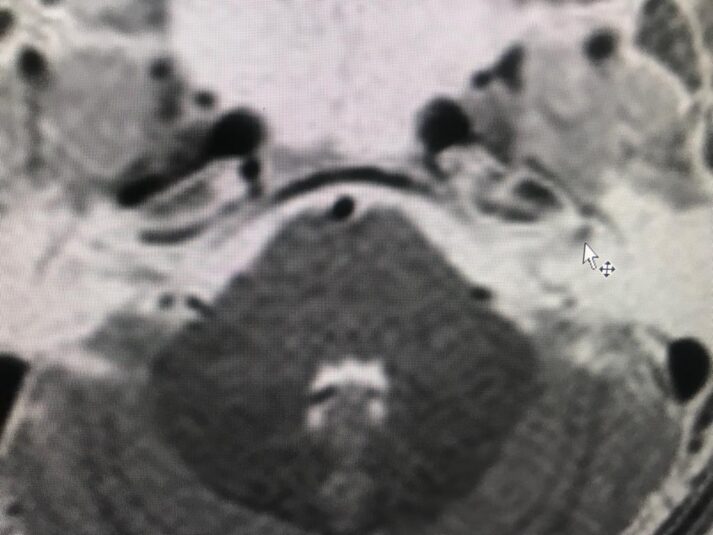

Caso: Neuritis del nervio facial izquierdo. RM cerebral.

Dra. Sterling Arróliga Selva

Lic Francisco Paseta.

Ing Lesther Lira.